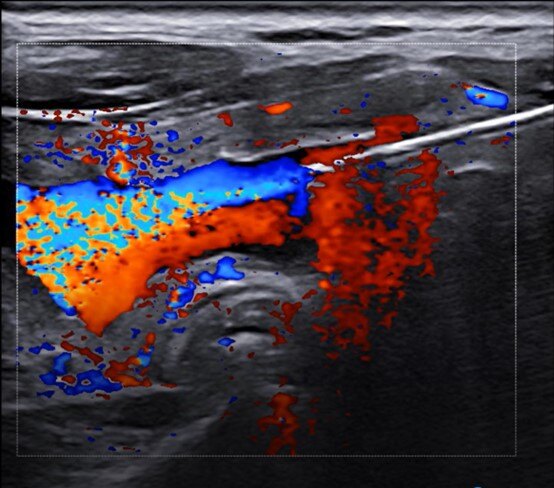

你是否聽說過甲狀腺囊性為主結節(jié)的超聲引導下硬化治療?這項治療方法可以有效地幫助人們處理甲狀腺相關問題。本文將為你詳細介紹這一治療方法的原理、過程和效果。1.了解甲狀腺囊性結節(jié)首先,我們來了解一下甲狀腺囊性結節(jié)是什么。甲狀腺是位于頸部前方的一個小腺體,它負責產生激素來調節(jié)身體的新陳代謝。當甲狀腺發(fā)生異常生長時,會形成結節(jié)。有些結節(jié)是囊性的,也就是內部充滿液體,而非實心的腫塊。2.超聲引導下硬化治療的原理結節(jié)硬化治療是通過向結節(jié)內注射硬化劑來使結節(jié)發(fā)生纖維化和萎縮的治療方法。這種治療的目的是減小或消除結節(jié)的大小,并改善患者的癥狀。結節(jié)硬化治療通常適用于那些不需要手術切除的囊性為主的良性結節(jié)。3.治療過程在治療開始之前,你將會接受甲狀腺超聲檢查,以確定結節(jié)的類型和位置。這有助于醫(yī)生決定是否適合進行超聲引導下硬化治療。當你準備好開始治療時,醫(yī)生會先給你消毒鋪巾,然后使用超聲儀器來引導注射針頭到達囊性結節(jié)內部,先將囊液抽出,根據情況決定是否使用生理鹽水沖洗。隨后,醫(yī)生會將硬化劑注入囊內進行沖洗,使囊壁黏連并最終萎縮。整個治療過程通常持續(xù)10-30分鐘,取決于結節(jié)的大小和數量。治療過程中幾乎沒有太大的感覺,整體上來說,這是一種相對較為安全且無痛的方法。4.效果和風險超聲引導下硬化治療可以有效地縮小或消除甲狀腺囊性為主結節(jié)。大多數患者都能夠在一次治療后看到明顯的改善,少部分患者需要2次治療,并且不需要住院治療。然而,像任何其他醫(yī)療過程一樣,超聲引導下硬化治療也有一些潛在風險。最常見的副作用包括術后幾天內嗓音變化、局部疼痛和發(fā)熱等。但是這些副作用通常是暫時的,并且會在幾天內消失。5.結論甲狀腺囊性為主結節(jié)的超聲引導下硬化治療是一種有效和安全的非手術治療方法。它可以幫助患者緩解甲狀腺相關問題,并提高生活質量。如果你有甲狀腺囊性結節(jié)的問題,不妨考慮一下這種治療方式。時間:周五下午1:30-4:00地點:瑞金醫(yī)院總院12號樓3樓超聲介入2診室掛號:超聲科-專病掛號-消融專病門診

囊腫,顧名思義,就是一個囊狀的物體局部突起,形成包塊,內容物常為液體滲出。氣球,大家都玩過吧,里面加點水,局部加壓擠出來一個小球樣的突起,這就是囊腫。囊腫可以長在體表,也可以長在內臟,如“甲狀腺囊腫”、“肝囊腫”、“腎囊腫”、“卵巢囊腫”等,因為屬于良性疾病,基本不會癌變,所以小囊腫一般都不需要處理,每年定期檢查就行。但如果囊腫增大到一定程度,如直徑超過5cm則破裂風險較大,或者囊腫增大對周圍組織產生了壓迫,出現臨床不適癥狀,如腰酸、腹痛等,則需要進行干預治療了。囊腫的治療大致有3種,傳統(tǒng)外科手術切除、微創(chuàng)腔鏡開窗和介入穿刺抽吸硬化。傳統(tǒng)外科手術切除因為創(chuàng)傷大,基本已經淘汰。微創(chuàng)腔鏡開窗是通過腔鏡技術,在囊腫表面挖一個洞,讓囊液自己慢慢流出來然后機體吸收,創(chuàng)傷小了,但復發(fā)率較高,部分病人囊液外流也會造成組織感染。介入穿刺抽吸硬化,則是既有微創(chuàng)的優(yōu)點,又可避免高復發(fā)的風險。它是通過B超或CT引導,把一根細針穿刺進入囊內,針尾外界注射器抽吸干凈囊液,然后將無水酒精注射入囊內破壞囊壁分泌旺盛的細胞,這樣可以最大程度的減少復發(fā),整個治療過程創(chuàng)傷只有一個針眼。